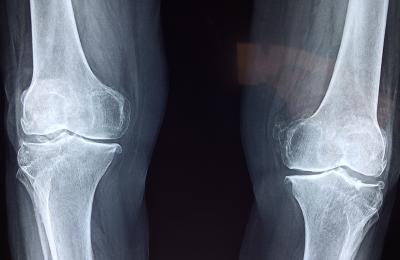

30.01.2022 Научно доказано е, че стареенето на ставите започва след 30-годишна възраст. Но въпреки това под внимание трябва да се вземат и други фактори, които могат да доведат до по-ранното им износване... |